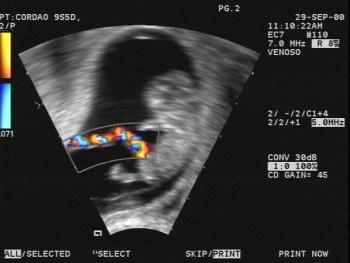

The mobile foraminal flap consisted of a thin membrane ballooning into the left atrium. During ventricular filling, the flap encroached on the mitral valve annulus, but did not appear to obstruct the mitral valve flow.